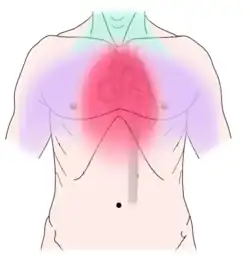

Non-dental causes of toothache are much less common as compared with dental causes. In a toothache of neurovascular origin, pain is reported in the teeth in conjunction with a migraine. Local and distant structures (such as ear, brain, carotid artery, or heart) can also refer pain to the teeth.[35]: 80, 81 Other non-dental causes of toothache include myofascial pain (muscle pain) and angina pectoris (which classically refers pain to the lower jaw). Very rarely, toothache can be psychogenic in origin.[10]: 57–58

Non-dental sources of pain often cause multiple teeth to hurt and have an epicenter that is either above or below the jaws. For instance, cardiac pain (which can make the bottom teeth hurt) usually radiates up from the chest and neck, and sinusitis (which can make the back top teeth hurt) is worsened by bending over.[10]: 56, 61 As all of these conditions may mimic toothache, it is possible that dental treatment, such as fillings, root canal treatment, or tooth extraction may be carried out unnecessarily by dentists in an attempt to relieve the individual's pain, and as a result the correct diagnosis is delayed. A hallmark is that there is no obvious dental cause, and signs and symptoms elsewhere in the body may be present. As migraines are typically present for many years, the diagnosis is easier to make. Often the character of the pain is the differentiator between dental and non-dental pain.

Establishing a diagnosis of nondental toothache is initially done by careful questioning about the site, nature, aggravating and relieving factors, and referral of the pain, then ruling out any dental causes. There are no specific treatments for nondental pain (each treatment is directed at the cause of the pain, rather than the toothache itself), but a dentist can assist in offering potential sources of the pain and direct the patient to appropriate care. The most critical nondental source is the radiation of angina pectoris into the lower teeth and the potential need for urgent cardiac care.[10]: 68